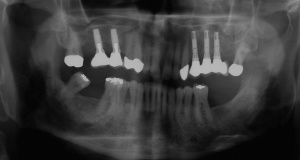

Ab dem Februar 2004 wurde der Patient zur Sicherung des Behandlungserfolges in das in der FU VIIa – Zahnmedizin seit 1996 praktizierte Recallsystem aufgenommen. Diese Erhaltungstherapie beinhaltet die bereits erwähnten Maßnahmen der Unterstützenden Parodontitistherapie (UPT). Aufgrund dienstlicher Erfordernisse (u. a. immer wieder Seefahrten des Patienten) konnte der zunächst geplante Abstand von vier Monaten nicht immer eingehalten werden. Ein Abstand von ca. sechs Monaten konnte jedoch trotz der teilweise schwierigen Rahmenbedingungen realisiert werden. Am Zahn 44 kam es im Jahr 2006 zu einem Rezidiv, sodass an diesem Zahn im September 2006 eine Lappenoperation durchgeführt wurde. Der intraoperativ vorgefundene tiefe cirkuläre vertikale Defekt führte zur Einschätzung einer langfristig fraglichen Prognose von 44. Im Zuge der weiteren Erhaltungstherapie zeigten sich bis auf 44 die parodontalen und periimplantären Gewebe völlig unauffällig: So betrugen die Sondiertiefen bei entzündungsfreien klinischen Verhältnissen durchweg zwei bis drei Millimeter. Auch radiologisch zeigten sich keine Auffälligkeiten. Es gab keine Progredienz der ehemaligen parodontalen Erkrankung, die Osseointegration der Implantate zeigte keine Veränderungen (s. Abb. 7). Erhöhte Sondiertiefen verblieben lediglich am Zahn 44. Nachdem sich trotz regelmäßiger Nachsorge an 44 keine Entzündungsfreiheit der marginalen Gingiva erzielen ließ und die Zahnlockerung von 44 zunehmend stärker wurde, erfolgte im Jahre 2010 die Entfernung des Zahnes und der Ersatz durch eine implantatgetragene Krone (s. Abb. 8). Die Erhaltungstherapie wurde fortgeführt, Behandlungsmaßnahmen über die Inhalte der UPT hinaus waren bis zur Entlassung des Soldaten im Jahre 2012 nicht erforderlich. Der Patient blieb jedoch auch nach der Entlassung aus dem aktiven Dienst Patient des Hauses, sodass die Erhaltungstherapie in der FU VIIa – Zahnmedizin fortgeführt werden konnte. Im April 2013 stellte sich der Patient mit Beschwerden am Zahn 45 vor, der Zahn wies zudem eine Lockerung des Grades II auf. Die durchgeführte Röntgendiagnostik (s. Abb. 9) zeigte eine Wurzelfraktur im apikalen Wurzeldrittel, ein Zahnerhalt von 45 war nicht möglich und der Zahn wurde noch in gleicher Sitzung entfernt. Zur Versorgung der Lücke wären verschiedene prothetische Lösungen möglich gewesen. Letztlich fiel die Entscheidung zugunsten eine Extensionsbrücke von regio 45 auf 48. So konnte die Implantatkrone 44 belassen und mit dem Lückenschluss mittels einer vergleichsweise einfachen und schnellen prothetischen Versorgung auch die Schaltlücke 46 geschlossen werden. Der Patient befindet sich nach wie vor in der FU VIIa in der Erhaltungstherapie, die Fotos zeigen den aktuellen klinischen Befund in der Aufsicht des Ober- und Unterkiefers (s. Abb. 10, 11).